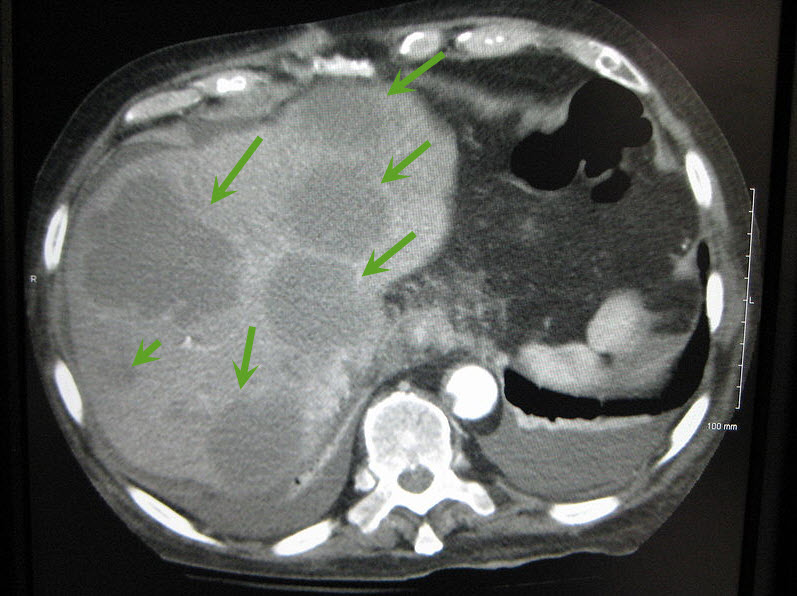

Click here or image for full size view

|

| Axial CT of the abdomen showing multiple liver metastases. Image courtesy of James Heilman, MD / Wikimedia Commons / CC-BY-SA-3.0 |

The majority of liver metastases present as multiple tumors. Only 10% of all cases present with a solitary metastatic lesion. Moreover, in more than three-quarters (3/4) of patients with liver metastases, there is involvement of both lobes of the liver.